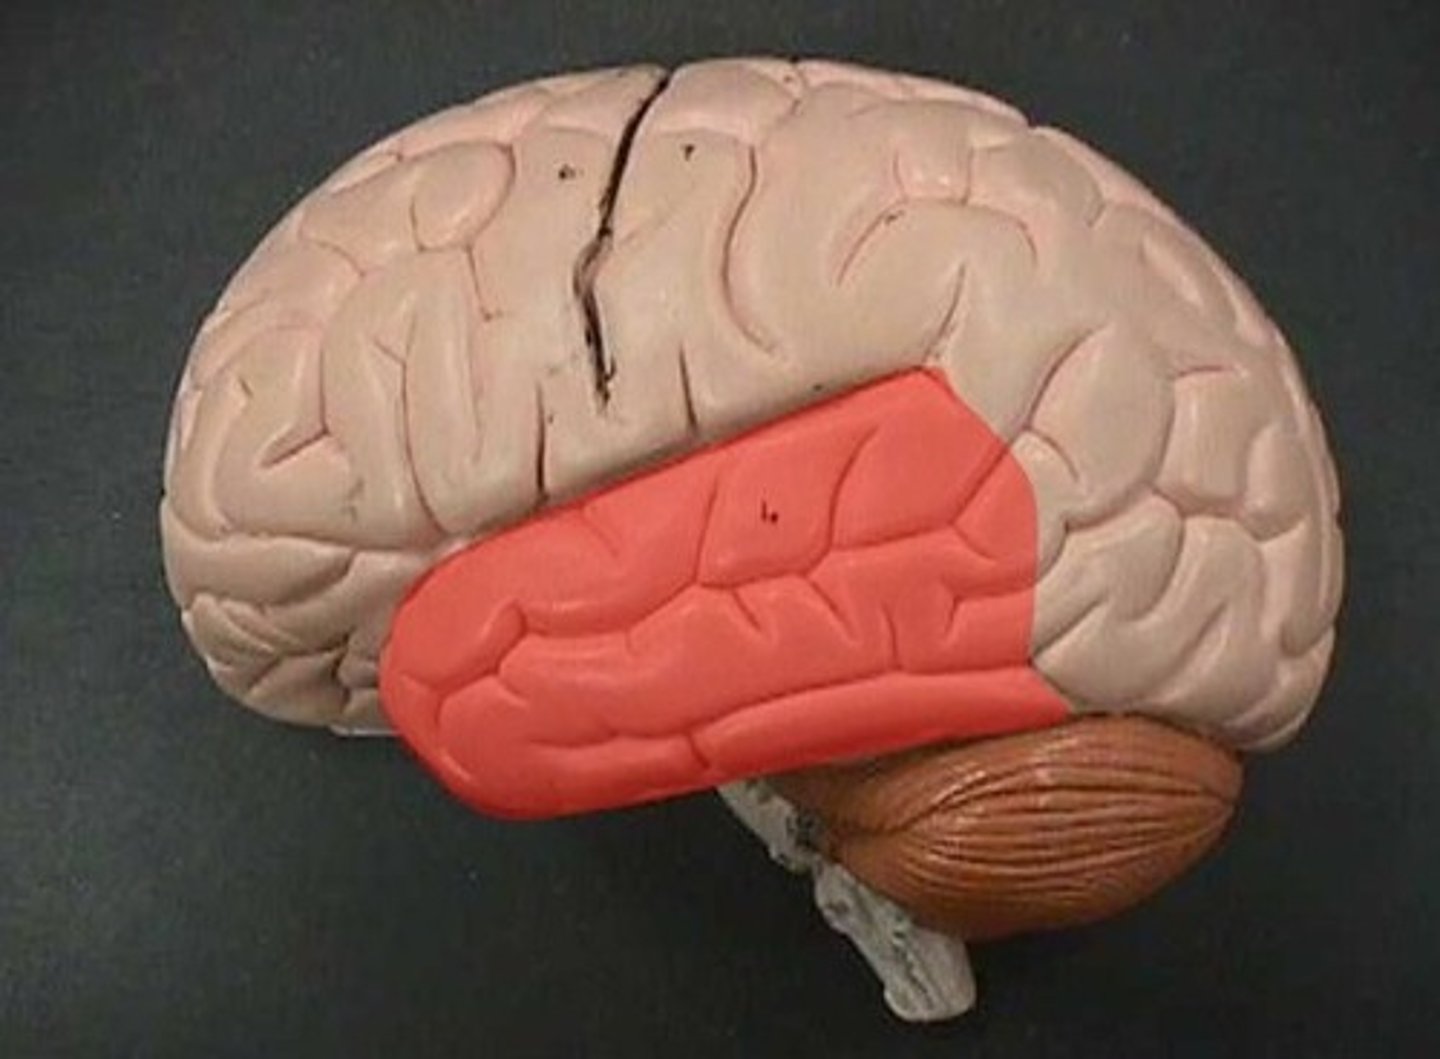

temporal lobe